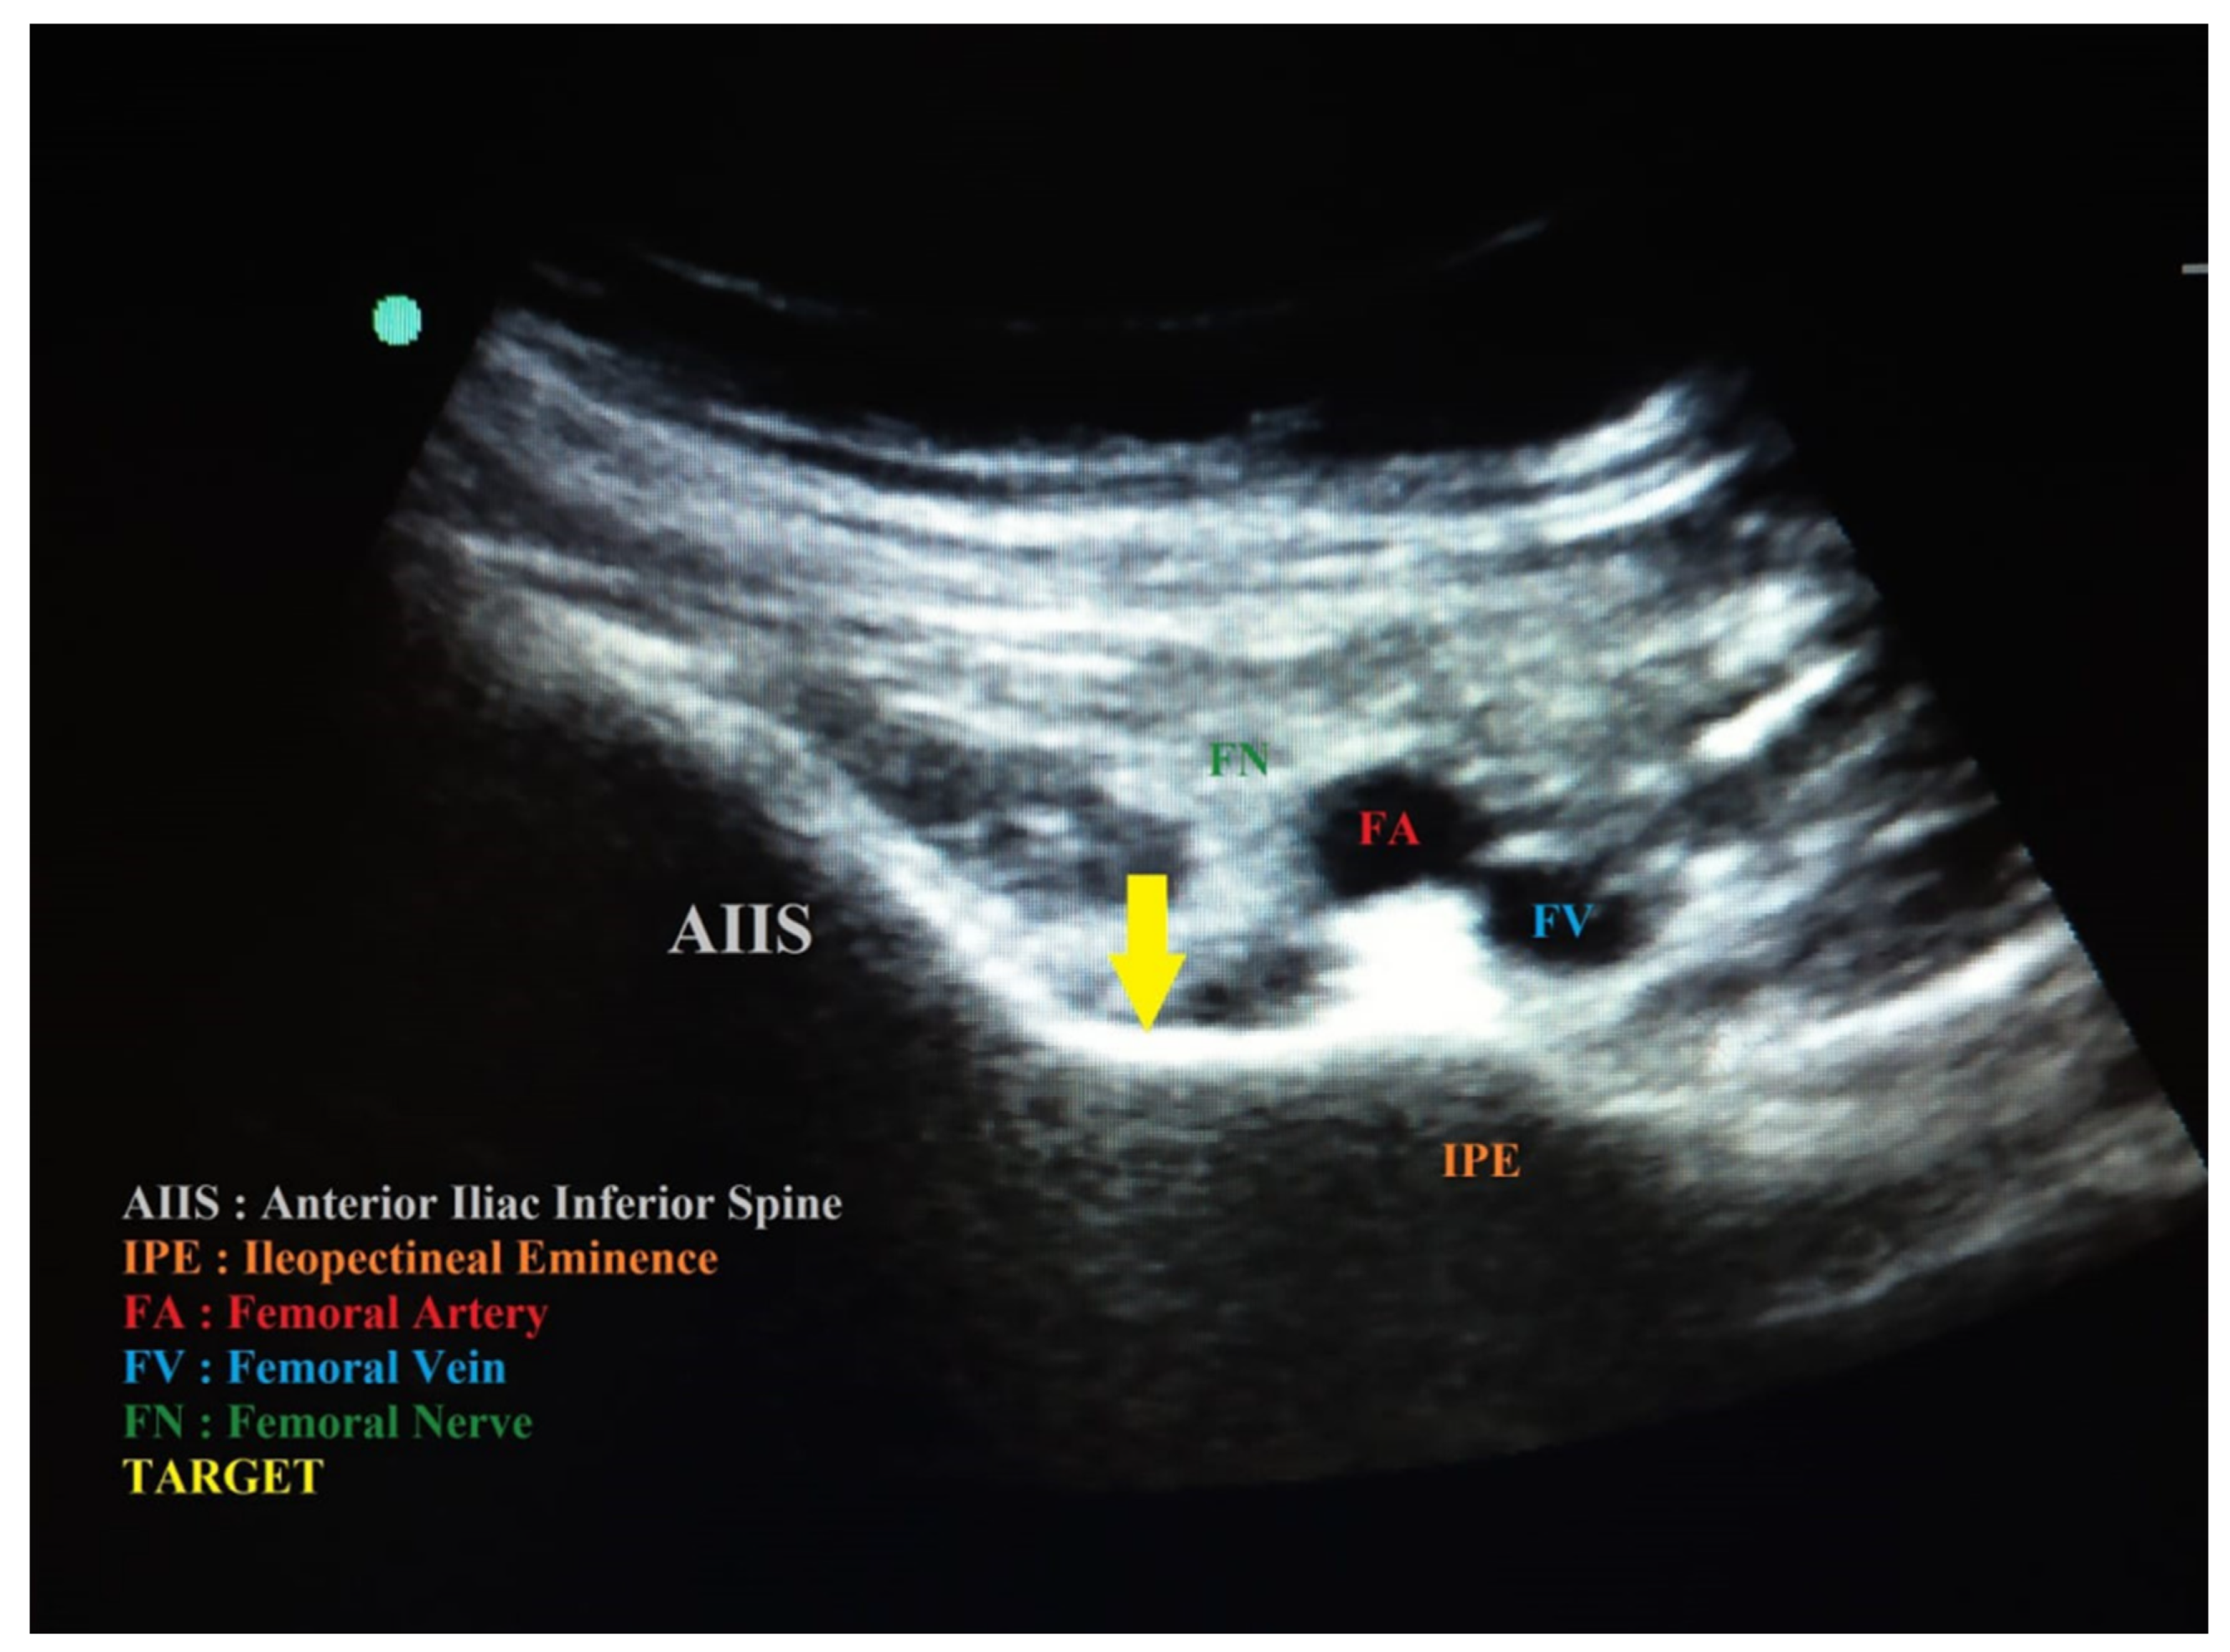

The FN blocks were performed with an ultrasound-guided technique, linear probe, and in-plane approach with a 21 G 50 mm needle by injecting 15 mL of 0.5% ropivacaine + 1% lidocaine with the addition of 4 mg dexamethasone. With the same probe, approach, and needle, the LFCN blocks were performed by injecting 5 mL of 0.5% ropivacaine. The PENG blocks were performed with a US-guided technique, convex probe, and in-plane approach; the probe was initially placed in a transverse plane above the AIIS and then aligned with the pubic ramus by rotating the probe approximately 45 degrees, thus visualizing the IPE, tendon and the iliopsoas muscle, the femoral artery, and the pectineus muscle [14]; a 21 G 50 mm needle was inserted in the latero–medial direction, positioning the tip in the muscle–fascial plane between the tendon of the psoas muscle anteriorly and the pubic branch posteriorly (Figure 1). After a negative aspiration of 20 mL, 0.5% ropivacaine + 1% lidocaine with the addition of 4 mg dexamethasone were injected as required by using internal protocols. Both techniques were performed with the patient in a supine position.

Figure 1.

PENG block with high frequency linear probe. The needle is outlined by a yellow dotted arrow.